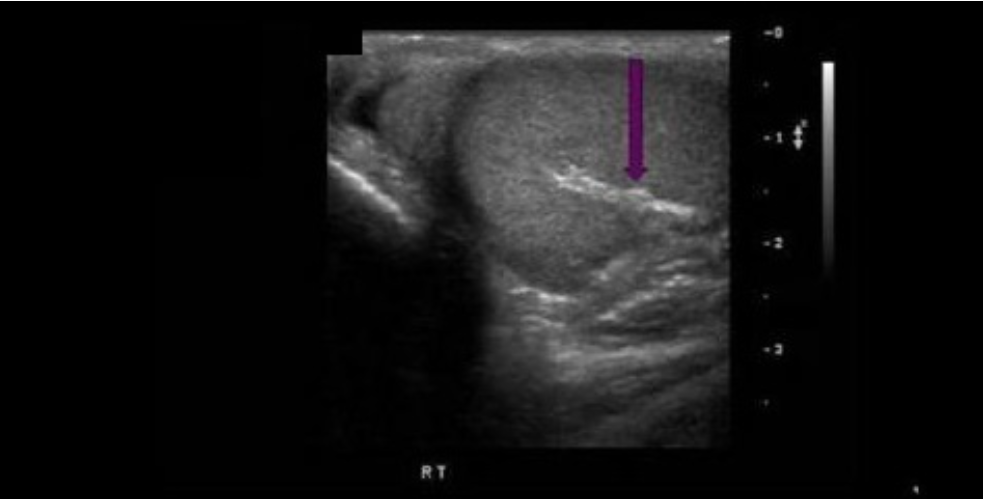

Which blood vessel is located lateral to the right lobe of the thyroid and demonstrates an anechoic circular shape in a transverse view of the mid thyroid?

C. right common carotid artery

The right common carotid artery is located lateral to the right lobe of the thyroid and demonstrates an anechoic circular shape in a transverse view of the mid thyroid.

The image displays the left lobe of the thyroid with the circular CCA immediately lateral to the mid lobe and ovoid IJV lateral to the CCA.